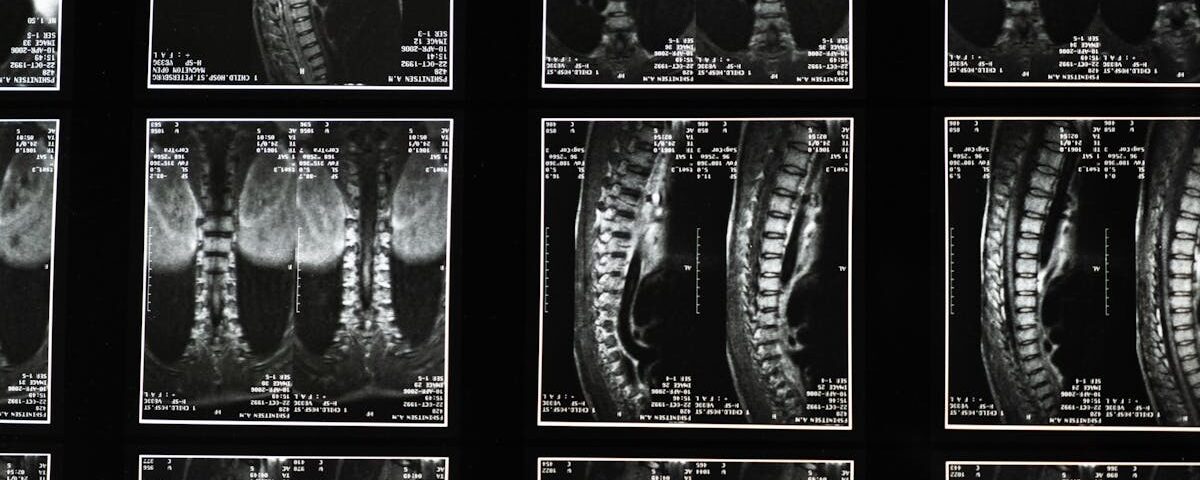

Diagnostic

IRM ou examens cliniques pour évaluer l’état du nerf crural.